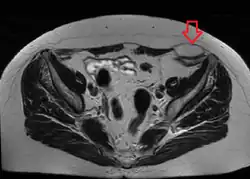

Die Spieghel-Hernie (lateinisch Hernia spiegheli, Hernia linea semilunaris oder Hernia ventralis lateralis) ist eine Hernie (Bauchwandbruch), die sich im Bereich des hinteren Blattes der Rektusscheide (Linea semilunaris) in die Bauchdecke hinein erstreckt. Sie ist benannt nach dem flämischen Anatomen Adriaan van den Spieghel (1578–1625).

Durchbruch von Bauchinhalt durch die Bauchwand. Die Bruchpforte liegt zwischen der Faszie des M. transversus abdominis bzw. M. obliquus internus (lateraler Rand) und Rektusscheide (medialer Rand). Den lateralen Rand nennt man Linea semilunaris Spiegheli, da er eine halbmondförmige Kontur hat. Meistens treten die Hernien auf Höhe der Linea arcuata aus.

Kleine Spieghel-Hernien sind in der klinischen Untersuchung nicht immer tastbar, zusätzlich kann die Diagnostik erschwert sein durch Adipositas. Sonographie (Ultraschall-Untersuchung) und falls nötig Computer- oder Kernspintomographie sichern die Diagnose.